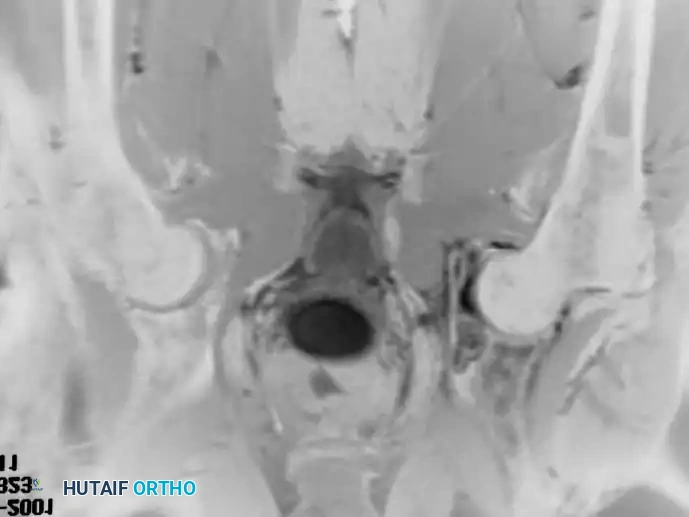

Intraoperative Imaging and Margin Assessment

Continuous intraoperative assessment using fluoroscopy and frozen section pathology is mandatory. The following images demonstrate various stages of complex upper extremity resections, allograft preparations, and prosthetic implantations across the humerus and elbow joint.